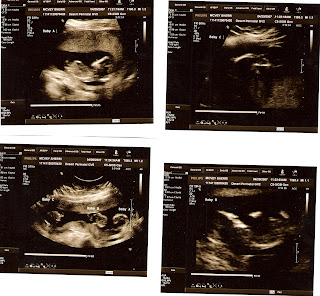

We have an office visit on 4/20/07 to check on the babies before the cerclage. Babies are great, growing well.